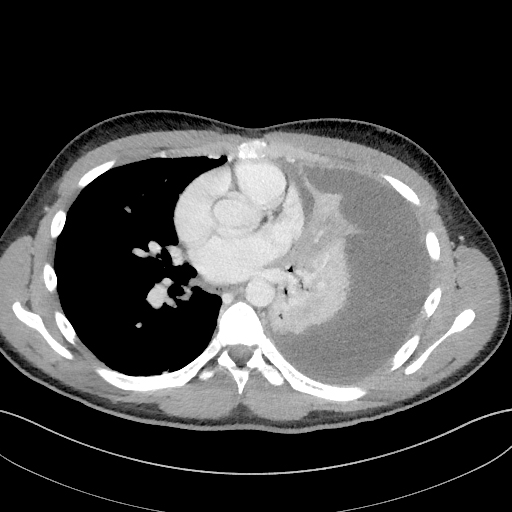

En uke senere var allmenntilstanden fortsatt god, men han ble økende hypoksisk med oksygenmetning ned mot 90 %. Til tross for behandling med cefotaksim intravenøst i syv døgn, var CRP 199 mg/l. CT thorax viste at nær hele venstre thoraxhule var fylt med ekspansivt preget pleuravæske og funn forenlig med pneumoni i tilliggende atelektatisk venstre underlapp (fig 1).